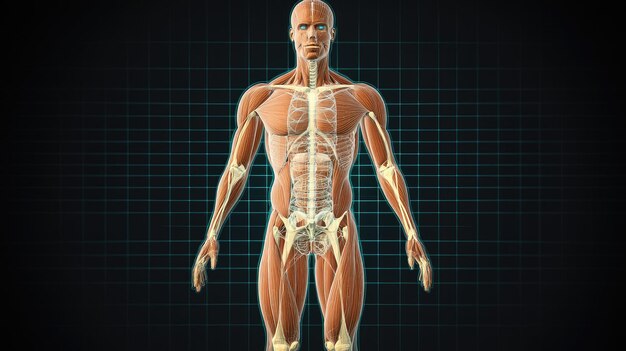

Human Anatomy Muscular And Skeletal System 3D Mode 409349625

14/11/2025

ร่างกายมนุษย์